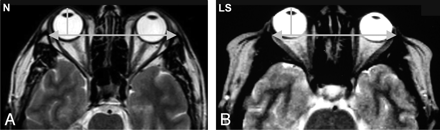

Axial T2-weighted images of the orbits. The measured parameters are demonstrated as follows: A, interzygomatic distance; B, distance from line A to the anterior globe; C, distance from line A to the posterior globe surface; D, angle of the orbit; E, length of the lateral wall of the orbit; F, diameter of the globe; G, anterior diameter of the orbit; H, interorbital distance; and I, distance from line G to the anterior surface of globe.

We measured the following parameters (Fig 1): axial diameter of the globe (F), interzygomatic distance (A), perpendicular distance from the interzygomatic line to the anterior margin of globe (B), perpendicular distance from the interzygomatic line to the posterior margin of the globe (C), medial-to-lateral diameter of the orbit at the anterior orbital rim (G), distance from the anterior orbital rim to the anterior globe (I), maximal distance between the medial walls of the orbits (H), lateral orbital wall angle (D), lateral orbital wall length (E), and mediolateral thickness of the intraorbital fat in the most cranial image of the orbit. We calculated the ratio of the length of the lateral orbital wall to the diameter of the globe and the ratio of the diameter of the orbit at the anterior orbital rim to the diameter of the globe. All measurements were made bilaterally.